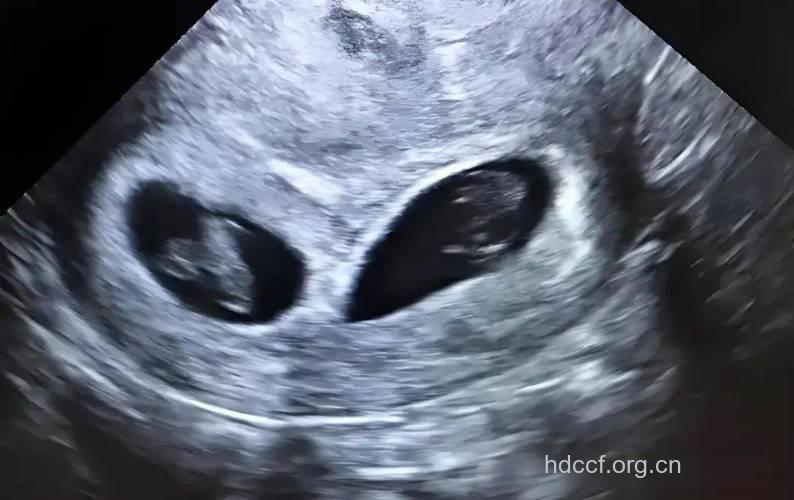

34周时,宝宝的肺部功能就很完善了。最后几周宝宝的主要工作是进行脂肪的累积和体重的增加。通常双胞胎的出生体重在5.5磅左右。

34周的时候医生会对胎位特别的关注,因为胎位正确与否关系到孕妇能否正常分娩。胎位如果是臀位,即胎儿的臀部朝下,既是胎位不正,要在医生的帮助下进行纠正,以便顺利生产。如果准妈妈是初产妇,那么这时胎儿部大多已降临骨盆,紧压在子宫的颈口。而经产妇的胎儿入盆时间会较晚一些,有的产妇在分娩前胎儿才会入盆。也许这个时候你的腿脚肿得更厉害了,这时也不要限制水分得摄入量,因为母体和胎儿都需要大量的水分。

34周的宝宝虽然已经基本发育成熟,但跟足月的宝宝比起来,身体的机能还是有差距的,要尽量避免因外界刺激造成早产,因此准妈妈要多注意宝宝的活动情况,每天都要数胎动,定期到医院做胎儿检测也是必要的。